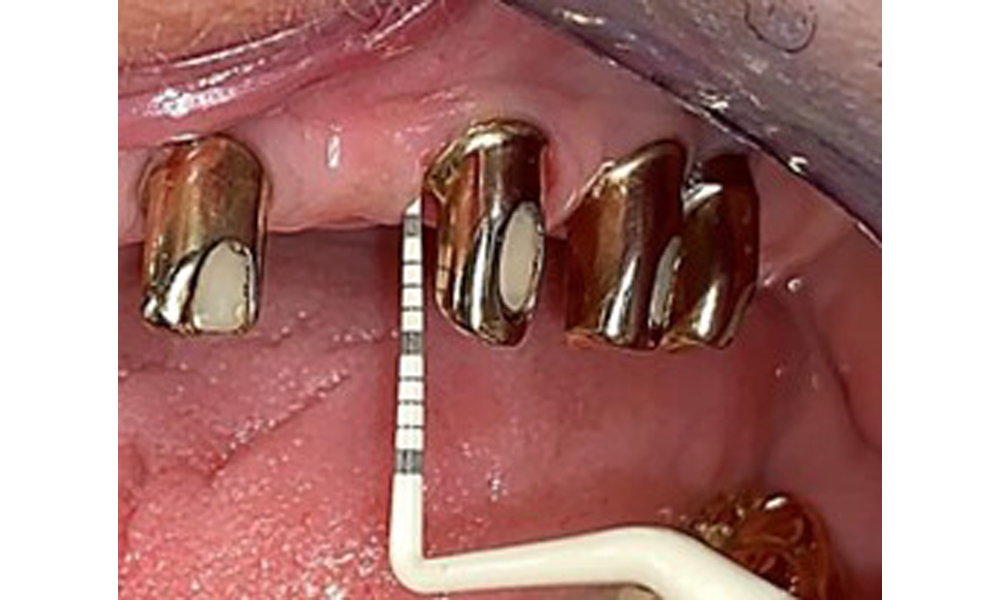

Okklusalansicht: Oberkiefer mit Zahn- und implantatgetragenen Teleskopen.

Abb. 2: Okklusalansicht: Oberkiefer mit Zahn- und implantatgetragenen Teleskopen.

Der dentale Befund stellt sich wie folgt dar: Kombinierte herausnehmbare Implantat- und zahngetragene Teleskoparbeit auf Implantaten 15, 13, 21, 23, 24, 25 und Zahn 11 (Abb. 1, Abb. 2, Abb. 3). Im Unterkiefer ist die Patientin mit einem festsitzenden Zahnersatz versorgt. 37–34 sowie 45–47 haben suffiziente Brücken (Abb. 4). Kronenränder sind intakt, aktive kariöse Läsionen sind nicht vorhanden. An Zahn 43 zeigt sich eine Compositefüllung mit Randspalt. Im Unterkiefer liegen Rezessionen mit freiliegender Wurzeloberfläche zwischen 1 – 3 mm vor. Dies trifft auch für 11 zu.

Einmal jährlich ist ein ausführlicher Parodontalstatus durchzuführen. Er dient zur umfangreichen Befunddokumentation zum Zustand des Parodonts und der Implantatsituation mit u. a. Taschentiefen, parodontaler Rezession, Furkationsbefall. So kann rechtzeitig auf eine mögliche Mucositis, Gingivitis bzw. Parodontitis oder Periimplantitis reagiert werden. Die Implantatsondierung ist mit einer Kunststoffsonde zu empfehlen. Im vorliegenden Fall zeigt das Implantat 23 mesial eine Sondierungstiefe von 4 mm. Dabei ist weder Suppuration noch Blutung festzustellen, weswegen hier keine Periimplantitis vorliegt.

Die Patientin hat eine stabile parodontale Situation. Es zeigen sich eine entzündungsfreie Gingiva und entzündungsfreie periimplatäre Weichgewebe. Die Sondierungstiefen liegen bei 1–3 mm im physiologischen Bereich. Es zeigen sich generalisierte Rezessionen von 1–3 mm. Implantat 23 hat eine erhöhte Sondierungstiefe von 4 mm ohne Anzeichen auf Sekret oder Blutung (Abb. 6). Der BOP liegt insgesamt bei 12 %.